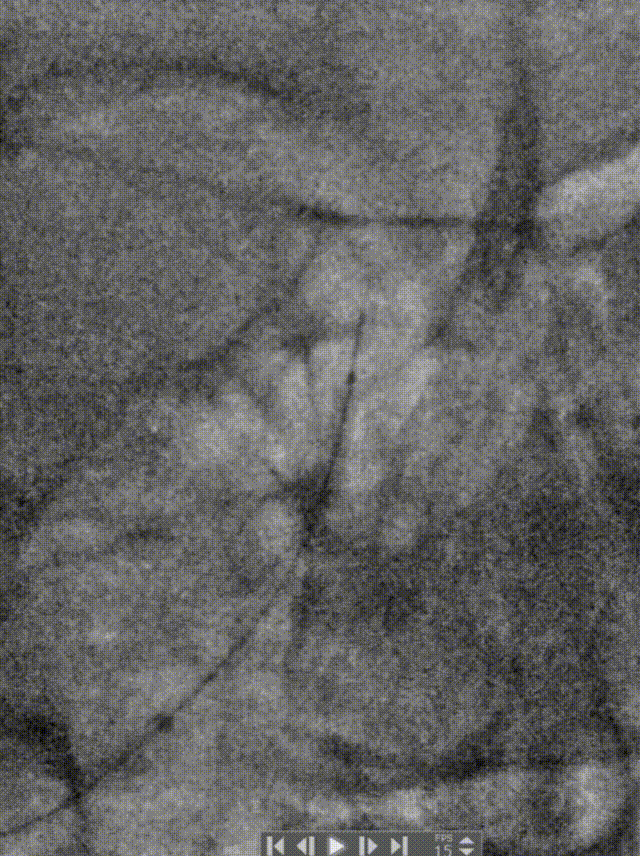

充盈球囊支架释放。

术后造影:基底动脉狭窄消失,双侧AICA通畅。